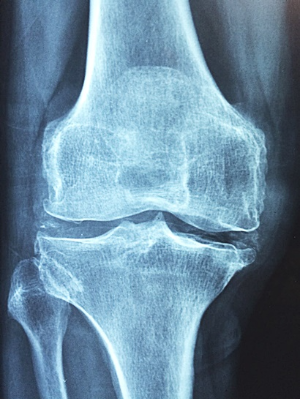

6. 퇴행성 관절염

퇴행성 관절염은 나이가 들어가면서 뼈, 인대, 근육 등의 조직이 퇴행하고 연골이 점차적으로 닳아서 염증이 발생하여 통증을 유발하는 상태를 말합니다. 주로 노년층에서 발생하는 이 질환은 노화와 밀접한 관련이 있습니다. 대부분 무릎에서 증상이 나타나지만, 어깨, 손가락, 척추 등 다른 관절 부위에서도 발생할 수 있어 항상 주의해야 합니다.